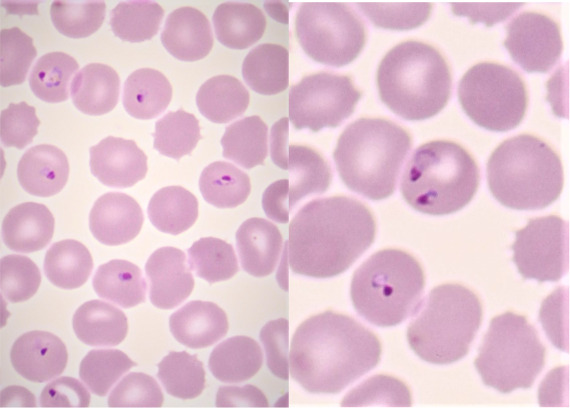

plasmodium falciparum stadia schizogonii krwinkowej

plasmodium falciparum stadia schizogonii krwinkowej